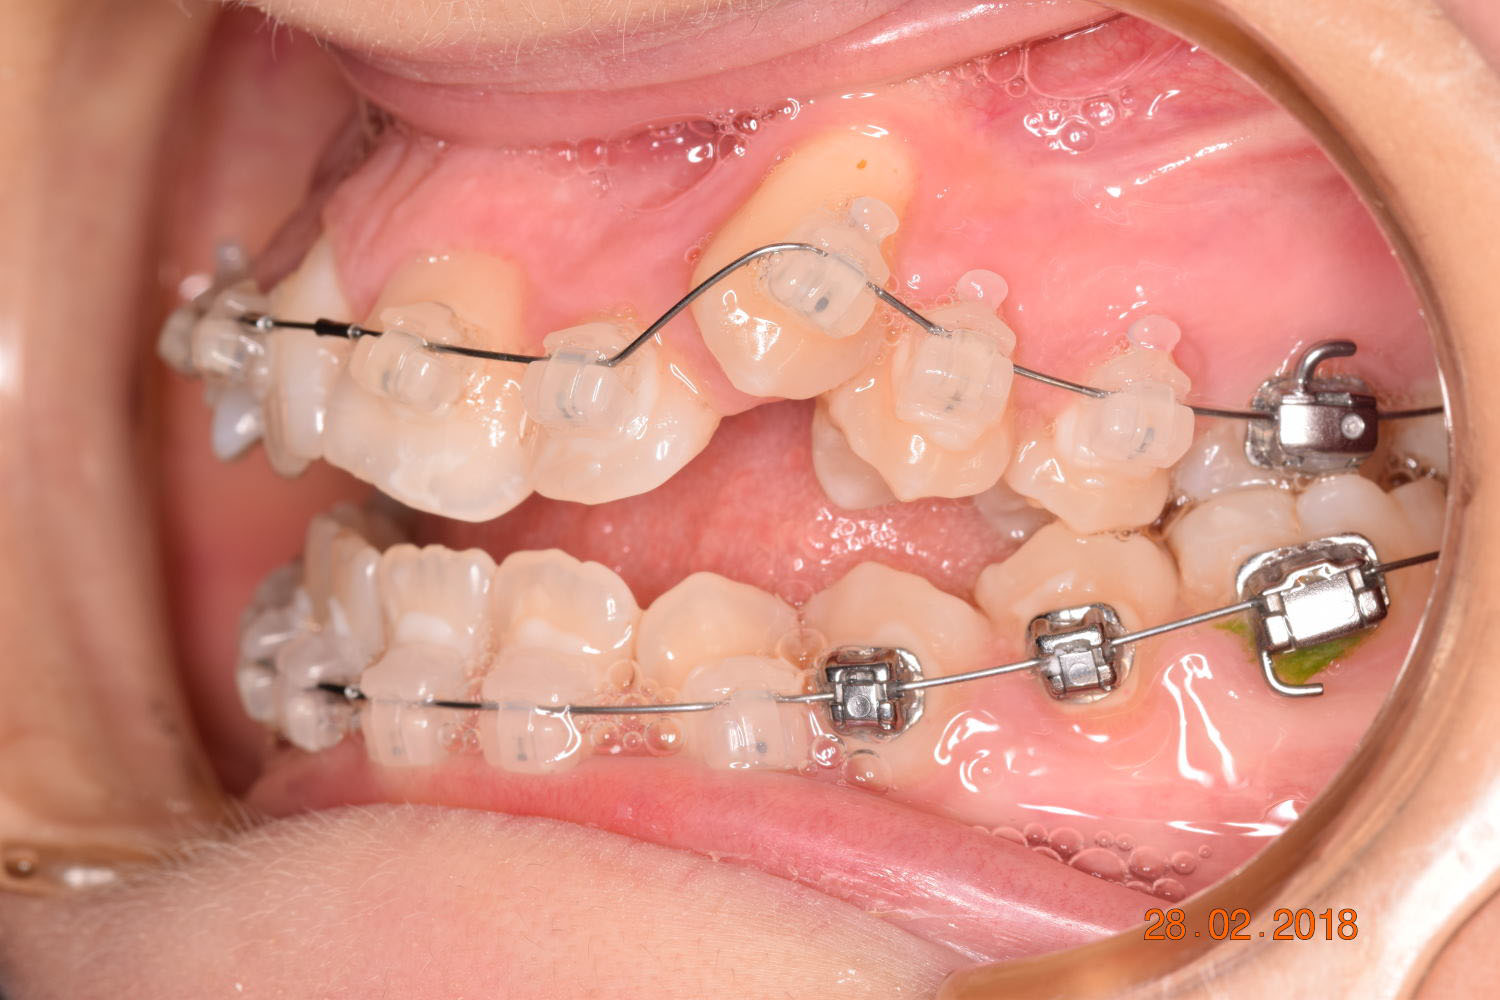

The treatment began in 2017. Given the patient’s preference for less visible brackets, Damon Clear brackets were selected. High torque upper cuspids and low torque upper incisors were chosen to offer the best torque control for upper arch development. For the lower arch, there were no alternative bracket configurations available. Bite turbos were applied to the upper second molars.

Adhering to the principles of Face First Orthodontics, the primary objective was to increase midface support by expanding the upper maxilla, fixing the cross bite, and aligning the teeth. Closing the open bite was a secondary objective.

A 27-year-old female patient presented with class III malocclusion, 15 mm crowding in the upper arch, an anterior open bite, a lateral crossbite, and a total ABO score of 29. Her facial profile was straight with a retrusive maxilla, and the upper and lower incisors were retroclined. An extreme lack of midface support was also noted, and the constricted dental arches resulted in a poor smile width and dark buccal corridors. No myofunctional investigations were performed at the time, as they were initially considered unnecessary.